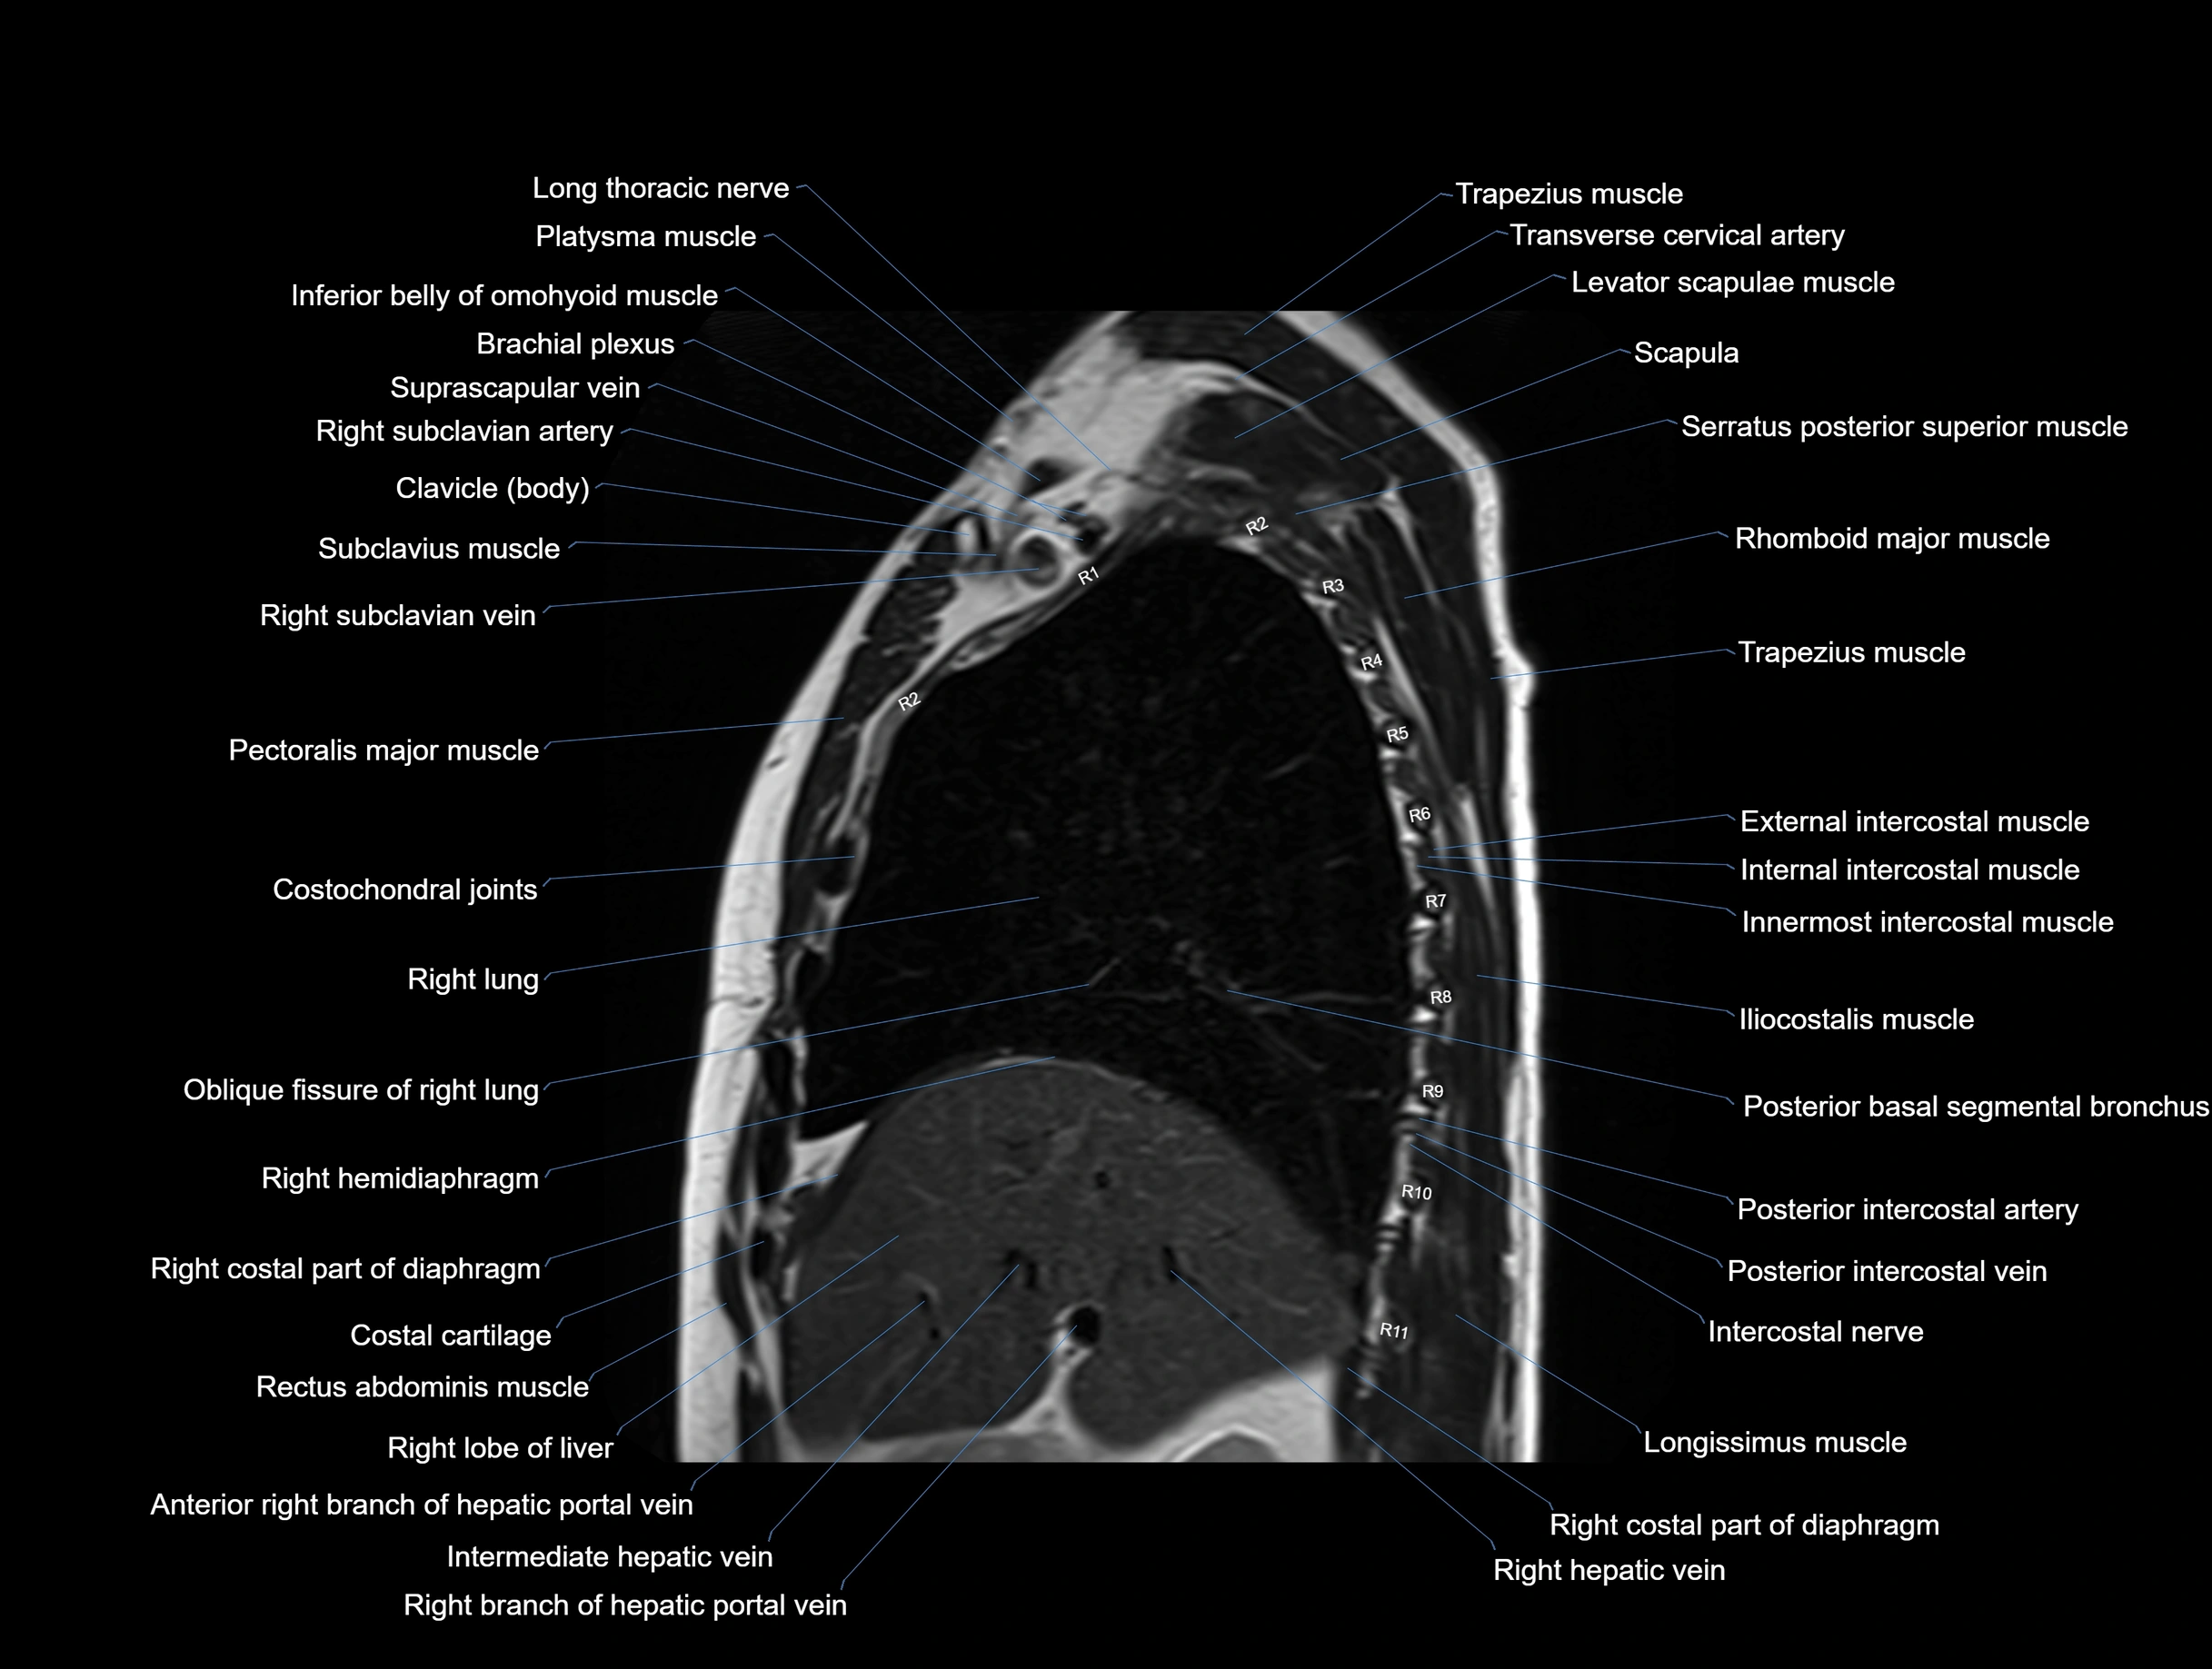

MRI images